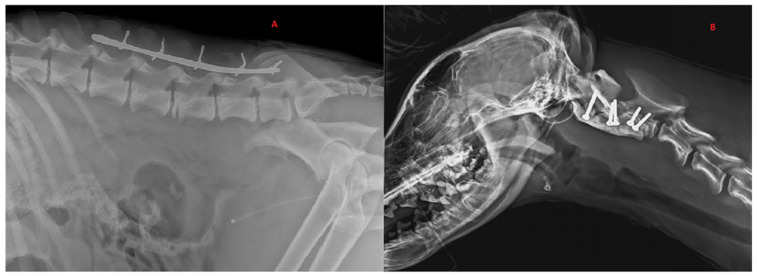

回顾了2017年至2022年在圣米歇尔Ospedale兽医医院治疗的14只C1至L7椎体骨折或脱位(SFL)的意大利狼(Canis lupus italicus)的医疗记录。导致SFL最常见的原因是“道路交通事故”。使用改良的Frankel量表将神经症状从0到6分级。C1-C5骨折1例,T3-L3骨折11例,L4-L7骨折2例。6只狼在没有治疗的情况下被安乐死,因为它们表现出没有深度疼痛感知(DPP)的截瘫。两只有运动功能的动物被保守治疗,后来其中一只因为神经损伤而被安乐死。六只狼接受了手术治疗。7只狼的神经系统恢复良好,其中6只被放归野外。我们的研究结果表明,术前患有DPP的狼可能有良好的功能恢复。

The medical records of 14 Italian wolves (Canis lupus italicus) with a vertebral fracture or luxation (SFL) between C1 and L7 treated at Ospedale Veterinario San Michele from 2017 and 2022 were reviewed. The most common cause of SFL was "road traffic accident". Neurological signs were graded from 0 to 6 using a modified Frankel scale. Spinal fractures occurred in C1-C5 in 1 case, in T3-L3 in 11 cases and in L4-L7 in 2 cases. Six wolves were euthanized without treatment because they presented paraplegia without deep pain perception (DPP). Two animals with motor function were treated conservatively, and later on one of them was euthanized because of neurological impairment. Six wolves were surgically treated. Seven wolves had good neurological recovery, and six of them were released into the wild. Our results suggest that wolves with DPP before surgery may have a good functional recovery.